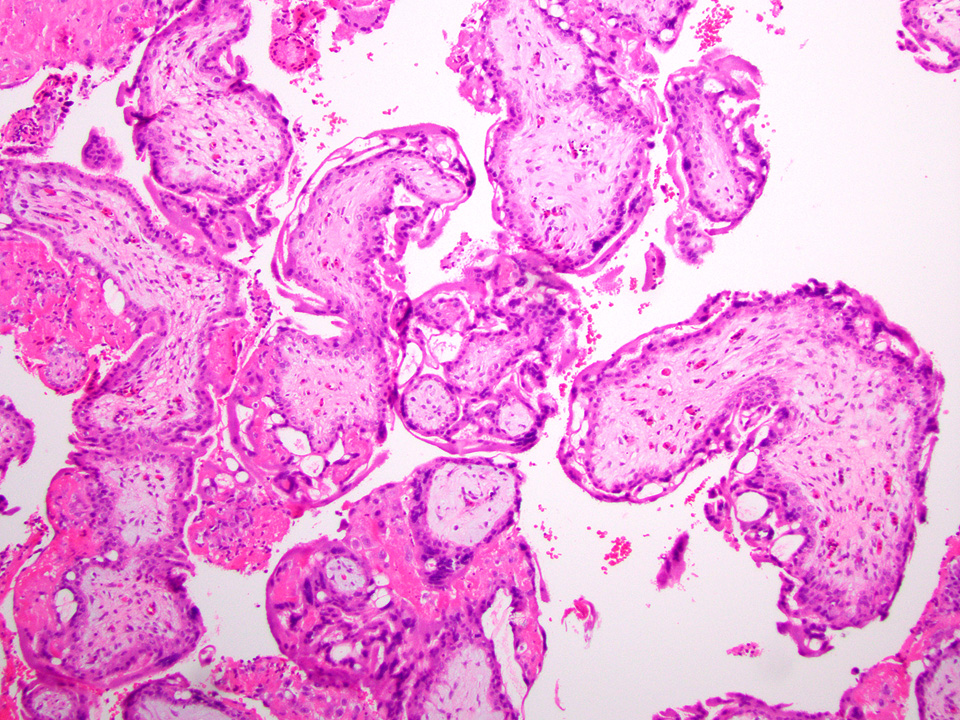

Microscopic (histologic) description

- Removed or passed products of conception may contain:

- Early first trimester chorionic sac (< 8 weeks): thin chorion and scant villi that are sparsely or nonvascularized

- Villous trophoblast is bilayered (mononuclear cytotrophoblast inner layer and multinucleated syncytiotrophoblast outer later) and circumferential with occasional polarized trophoblast protrusions

- Mid first trimester chorionic sac (8 - 10 weeks): may exhibit recognizable amnion, early stromal collagenization of chorion and proximal villi and increased volume of distal villi with distinct capillaries

- Later first trimester chorionic sac (> 10 weeks): may exhibit loose fusion of amnion and chorion, a more collagenized chorion and stem villi, more distinct walls of fetal vessels and numerous villi with increasing demarcation between proximal and distal branches

- Spectrum of villous changes in immature chorionic villi following embryonic death (Placenta 2005;26:114):

- Cellular debris within villous vessels - earliest change

- Villous edema with myxoid stromal degeneration - may be confused with molar gestation

- Collagenized avascular villi (villous sclerosis / fibrosis)

- Villous edema and sclerosis / fibrosis often coexist

- Other findings: prominent perivillous fibrin with prolonged retention or in medical abortions, otherwise pathologic

Microscopic (histologic) images

Contributed by Chrystalle Katte Carreon, M.D. and Drucilla J. Roberts, M.D.